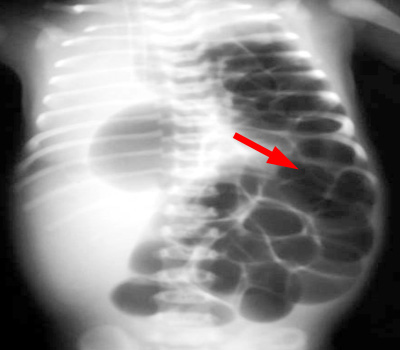

Question 5: The most likely diagnosis is:

Congenital diaphragmatic hernia. The cystic lucencies in the left chest are shown to be continuous with the bowel gas indicating a defect in the diaphragm with herniation of bowel into the chest.